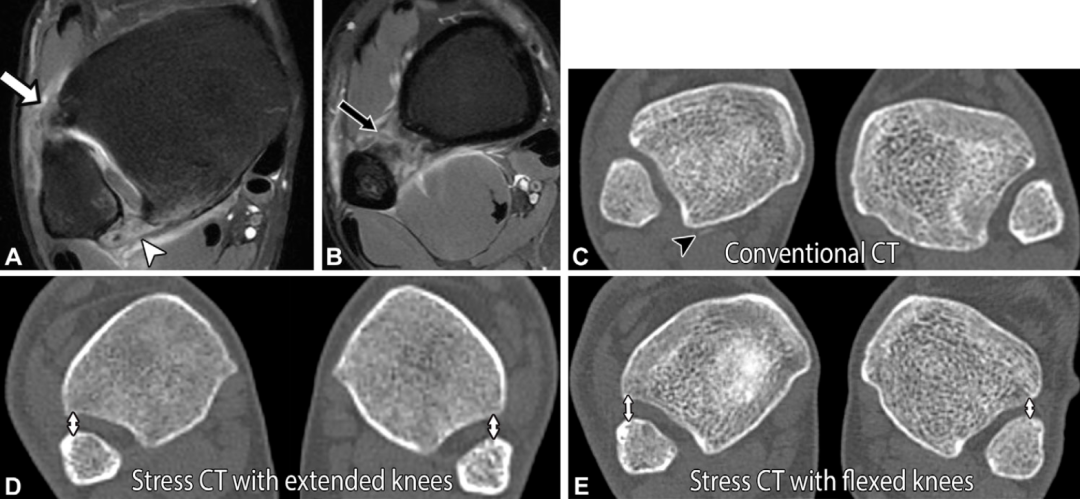

应力CT

常规CT无法模拟负重或应力状态,限制了其在关节不稳诊断中的应用。为克服这一局限性,近期有学者提出了三期应力CT检查方案:第一期在踝关节中立位扫描;第二期将踝关节外旋45°、最大背伸,膝关节伸直后扫描;第三期将踝关节外旋45°、背伸,膝关节屈曲45°后扫描。患者取仰卧位,扫描时足部由连接可调节应力绳的丙烯酸板支撑。本文作者发现,该应力操作有助于发现远端胫腓对位的细微变化,但受患者自主背伸的影响,检查中的机械应力存在不精确性和变异性:

有学者提出,当以患侧与健侧前内侧移位差值1mm为阈值时,应力CT对胫腓联合不稳的诊断效能良好。